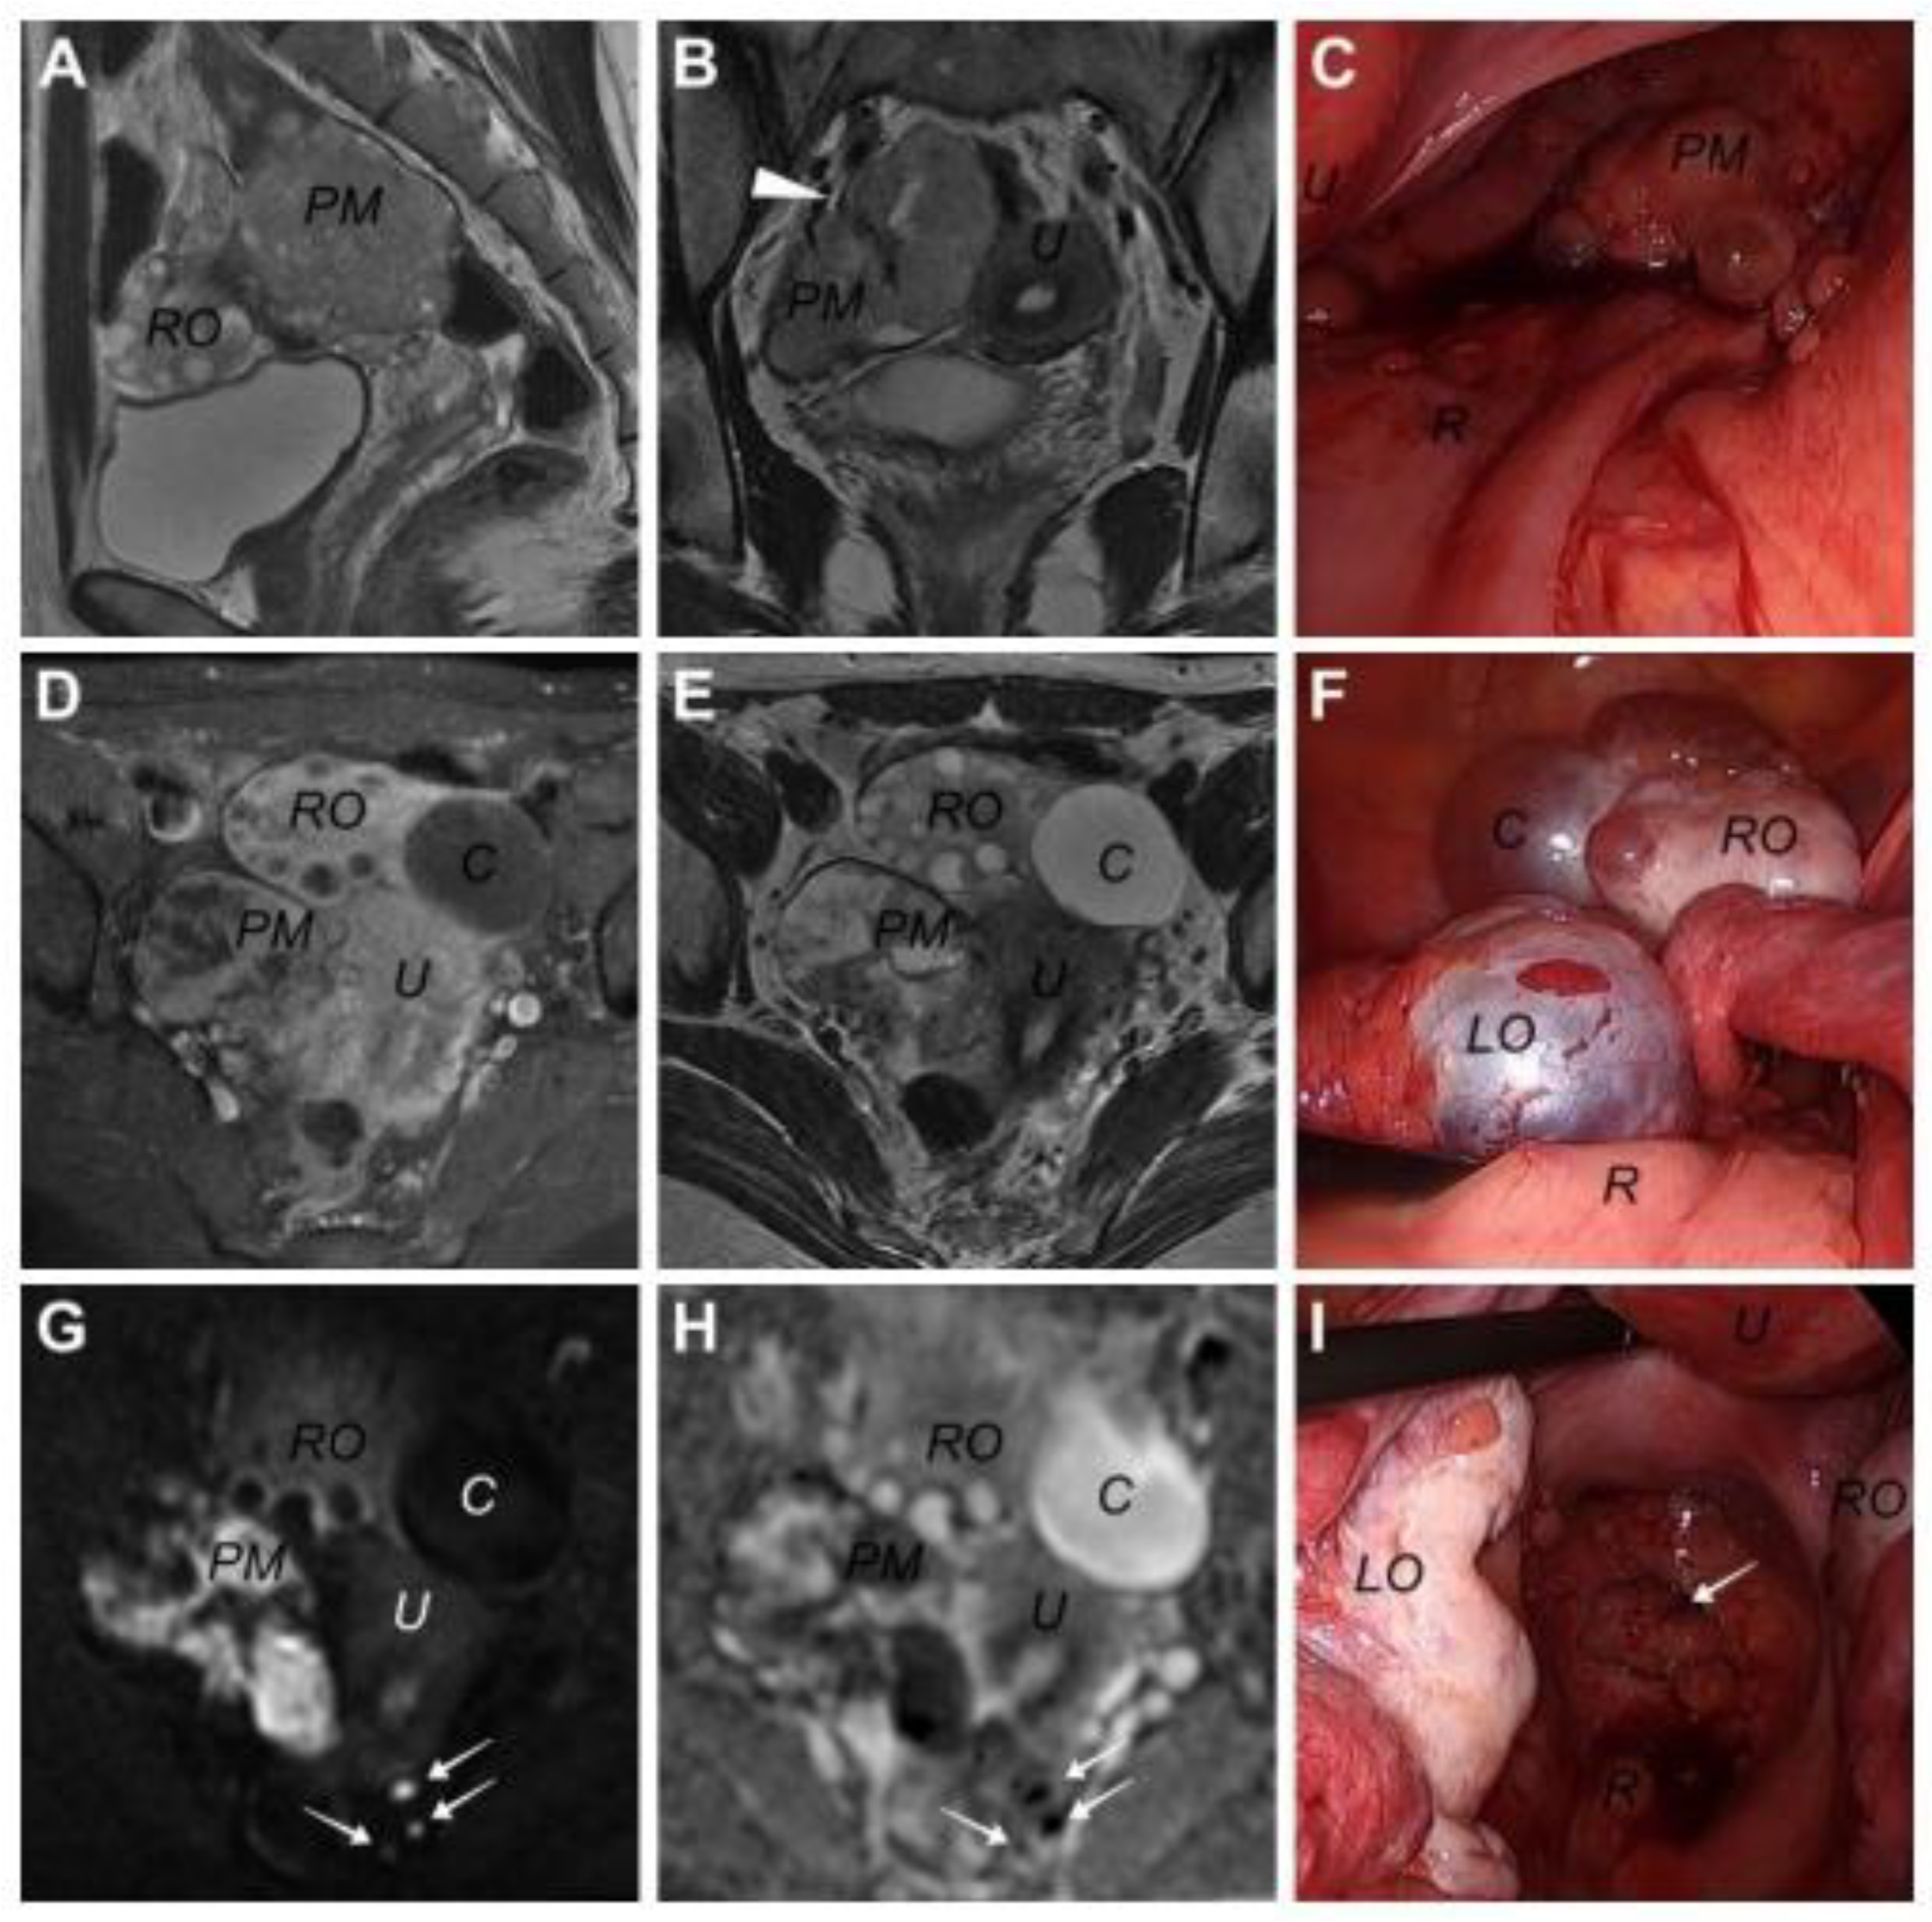

On 10 February 2023, a 31-year-old woman visited our institution with lower abdominal pain. The patient underwent laparoscopic unilateral ovarian cystectomy in another medical institution due to an unknown pathologic diagnosis approximately 4.5 years before the presentation. Whether surgical spillage occurred or not in this laparoscopic surgery was unclear. Computed tomography (CT) and subsequent magnetic resonance imaging (MRI) revealed a 6.5 × 4.0 cm multi-loculated cystic mass lesion arising from the right pelvic wall, along with a 4 cm sized cystic tumor in the right ovary (Figure 1). The pelvic mass was observed to be supplied by the right internal iliac artery in the coronary view of T2-weighted MRI (Figure 1B). Contrast-enhanced T1-weighted MRI revealed contrast enhancement throughout the pelvic mass, except for the internal cystic component (Figure 1D). The pelvic mass exhibited a high signal intensity (SI) on the diffusion-weighted MR image (b = 1000 s/mm2), and the apparent diffusion coefficient map showed a signal loss, indicating a highly cellular tumor (Figure 1G). Additionally, some lesions with similar SIs were observed in the rectal serosa, which were later confirmed as tumor seeding in laparoscopic exploration (Figure 1G,H). For this pelvic mass, a neurogenic tumor, such as a benign schwannoma, was suspected, whereas a benign cystic tumor and functional cyst were suspected in the right and left ovaries, respectively. No other abnormal findings, including ascites or lymphadenopathies, and the pancreas, were observed on MRI and CT. This study was approved by the Institutional Review Board of Kyungpook National University Hospital (KNUH 2023-06-015).

Figure 1.

Images of pelvic magnetic resonance imaging and laparoscopic findings in a 31-year-old woman diagnosed with primary solid pseudopapillary neoplasm (SPN) in this case. (A) Sagittal T2-weight image, (B) coronary T2-weighted image, (C) pelvic mass in laparoscopy, (D) contrast-enhanced T1-weighted image, (E) transverse T2-weighted image, (F) both ovaries in laparoscopy, (G) diffusion-weighted image, (H) the ADC map, and (I) metastatic lesions of the peritoneum in laparoscopy. (PM: pelvic mass, RO: right ovary, U: uterus, R: rectum, C: right ovarian cystic lesion, LO: left ovary, arrowhead: right internal iliac artery supplying the pelvic mass, white arrows: metastatic lesions on rectal serosa or peritoneum).

On 25 April 2023, the colorectal surgeon in our institution performed laparoscopic exploration. Intraoperatively, the surgeon detected seeding lesions on the rectal serosa and an isolated pelvic mass on the right side of the pelvic cavity. Moreover, the surgeon noted several small cystic or polypoid spherical mass lesions on the surfaces of both ovaries, fallopian tubes, and pelvic peritoneum (see Figure 1C, Figure 1F and Figure 1I, respectively). The mass was laparoscopically removed; subsequently, the surgeon called the gynecologic surgeon to examine the bilateral ovarian lesions. The capsules of the bilateral cystic lesions were resected and sent to a pathologist for frozen section analysis, which revealed the possibility of malignancy. Following permanent pathologic examination, both ovarian capsules and peritoneal lesions were diagnosed with solid pseudopapillary tumors. Following this diagnosis, whole-body positron emission tomography/CT was performed; however, no specific lesion in the pancreas or other distant organs was observed.